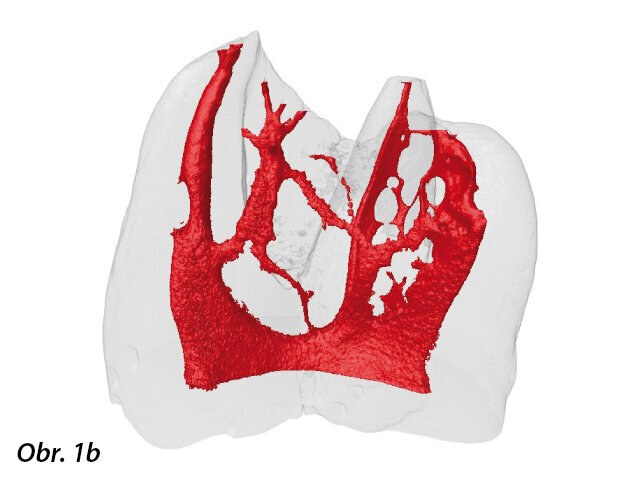

V tehdejších dobách se jednalo o radikální inovace a navzdory technologickým a biologickým nedostatkům dostupných nástrojů, které byly k dispozici, měly být tyto inovace technologicky realizovány a měly být odstraněny nedostatky ve vývoji materiálů a výrobních procesů; nicméně až donedávna se tak v podstatě nestalo. Abychom skutečně porozuměli vlastním nedostatkům, musí lékař poznat komplexnost toho, co je nezbytné k dosažení předvídatelného klinického úspěchu v endodoncii. Studie hodnotící průměrné rozměry apikální anatomie opakovaně prokázaly, že bukolingvální průměr je větší než meziodistální; kanálky jsou v převážné většině průběhu oválné, ne okrouhlé (obr. 1a, b).1-4

Tento axiální pohled na dolní molár demonstruje ovoidní excentricitu kanálků a existenci jistého spojení mezi meziobukálním a meziolingválním kanálkem v souladu s nálezy četných studií.